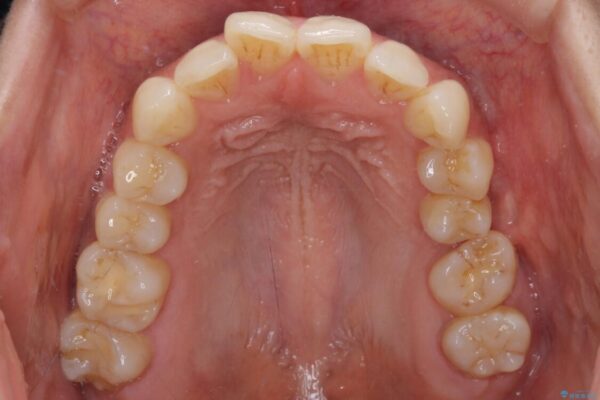

治療後

• インビザラインによる矯正治療と奥歯のインプラント治療 治療後画像